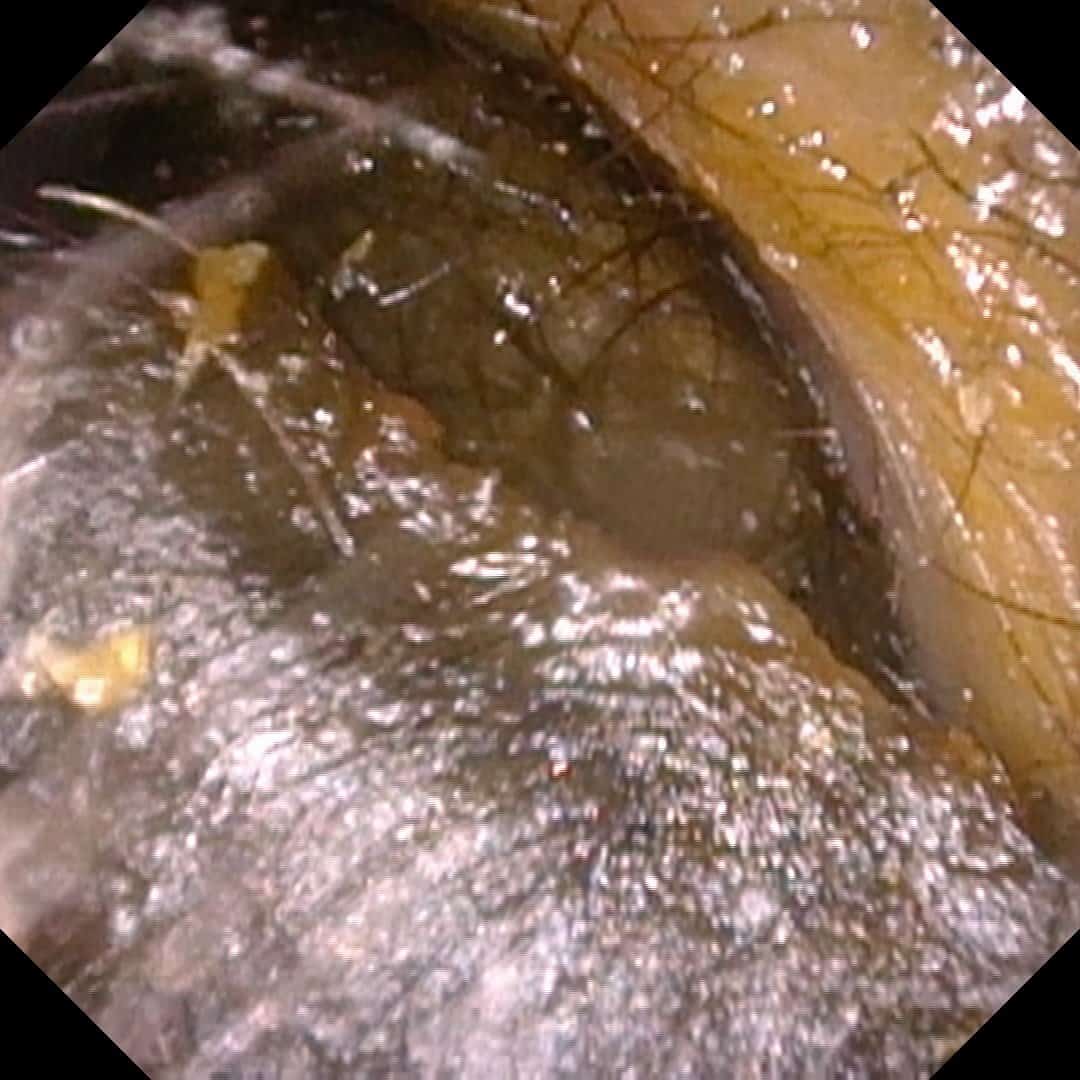

Ear wax impaction with hearing loss

Impacted Ear Wax